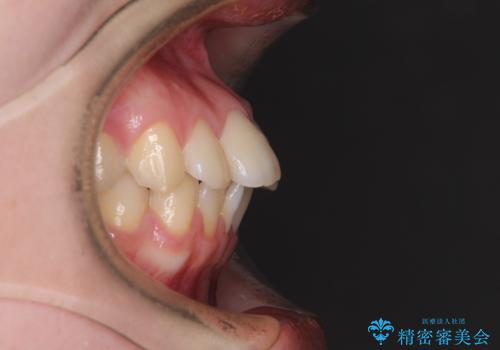

デコボコ歯列をきれいに インビザラインによる矯正治療

- 上下歯列全体のデコボコを気にして来院された患者様です。

主に下顎歯列全体の後方移動とIPR(歯と歯の間を削る)によってデコボコが解消するように設計し、インビザラインにより治療を行うこととしました。

1年半程度で終了するのではないかと予想しましたが、途中1年以上の来院がなく、トータルで3年の時間がかかってしまいました。

前歯のデコボコはより改善することが望ましい状態でしたが、患者様の希望により終了することとなりました。